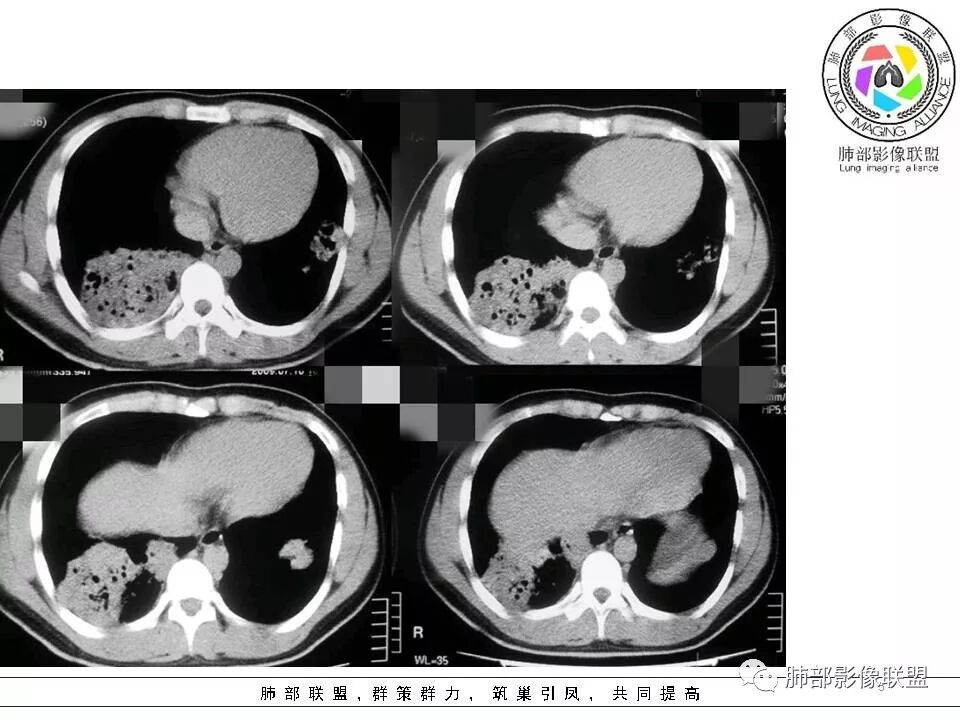

病灶的形态与分布如何?

右肺中叶及下叶大片实变影及双肺多发腺泡结节,局部成簇的腺泡结节融合成片,以外围及胸膜下分布为主

病灶的走行情况如何?

磨玻璃结节沿支气管飘散并落脚其他肺叶和肺段

病灶边缘情况如何?

以膨隆为主,局部稍平直、收缩

病灶内支气管情况如何?

支气管走形僵直、狭窄、中断,分支减少,呈“枯树枝”改变(图1-4红色短箭头)。可惜没有增强,不能了解病灶强化及血管情况。

病灶内的坏死情况?

有少许小空泡,未见明显液化坏死

周围肺野情况如何?

周围肺野有边界清楚GGO,局部中轴间质明显增厚并呈结节样改变(图1绿色箭头),树芽征不明显

老年男性,有发热、咳嗽、咳少量浓痰,呼吸困难,临床病程不详,但是影像上有实变、簇状分布的腺泡结节及枯树枝征,老年男性,高度怀疑肺炎型肺癌;肺炎型肺癌的病理基础是癌细胞沿肺泡壁、小叶中心、腺泡腔成簇、匍匐性生长,并沿肺泡孔及支气管播散,并且癌细胞分泌粘液引起肺组织实变,液化坏死少见,而干酪性肺结核多有虫噬样空洞及液化坏死区,结核支气管多为壁增厚 、扩张,肺癌的支气管多为狭窄堵塞、粗细不均。

温馨提示:病例2病理结果细支气管肺泡癌此定义取消,现归为腺癌,也是肺炎性肺腺癌的主要类型之一。详细内容请参考肺部影像联盟文章“不同时期腺癌的病理影像诊断”。